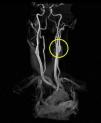

The patient returned for follow-up 3 months later. She reported the PCP and neurologist had, indeed, started her on oral warfarin based on our recommendations, and also continued her on the daily dose of 325mg aspirin to help prevent any ischemic attacks. The neurologist discontinued the hydrocodone and instead gave the patient oral gabapentin to manage her ongoing pain secondary to the ICAD. However, at the time of her 3 month follow-up visit with me she had since been instructed to discontinue her prednisone, warfarin, and gabapentin by her neurologist as her repeat MRI/MRA results from a few weeks prior had shown full resolution of her ICAD (see Figs. 5 and 6) and a drastic improvement in the caliber/lumen of the ICA. The patient was kept on 325mg daily aspirin by her PCP for prophylactic therapy. The patient reported her signs and symptoms had dramatically improved over the past few months and that she had not noticed any lingering ptosis or pupil abnormalities. She reported her neck pain and associated headaches had lessened in overall frequency as well. Snellen visual acuities at this 3-month follow-up appointment were stable at 20/20 OD and 20/20 OS without correction. Extraocular motilities were again full-range-of-motion with no signs of restriction OU. Confrontational visual fields were still full-to-finger-count OU. Pupils were equal, round, reactive to light OU with neither signs of APD OU nor light/near dissociation OU. Accommodative pupillary responses were normal OU as well. Pupils measured 5mm OD and 5mm OS in dark conditions and 3mm OD and 3mm OS in light conditions indicating resolution of her anisocoria. Interpalpebral fissure widths were equal in both eyes and measured 11mm OD and 11mm OS indicating resolution of the patient's ptosis. Intraocular pressures were measured at 16mmHg OD and 16mmHg OS via Goldman tonometry. The rest of the anterior segment and dilated fundus exams were completely unremarkable OU and consistent with her previous exams. The patient was instructed to follow up with her neurologist and PCP as directed for her ongoing care, and to follow up with our clinic in 6 months to monitor her ocular signs and symptoms.